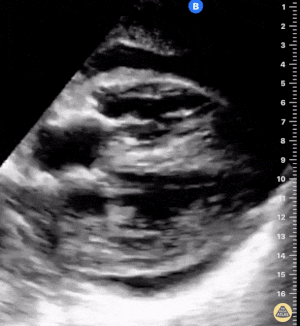

Sağ ventrikül fonksiyonunun değerlendirilmesi

Sağ ventrikül, önceki bölümde anlatılan temel kardiyak pencereler kullanılarak değerlendirilebilir. Normalde sağ ventrikül düşük basınçlı bir odacıktır ve sol ventriküle kıyasla daha küçük görünür.

Sağ ventrikül disfonksiyonunda özellikle şu bulgulara bakılır:

Sağ ventrikül dilatasyonu

Septal bombeleşme (septal bowing)

Kısa aks görüntüsünde, pulmoner arter basıncının artmasına bağlı olarak sağ ventrikül genişledikçe interventriküler septum sol kalbe doğru bombeleşir. Bu durum sol ventrikülde D-şekilli görünüm (D-sign) oluşturur.

Apikal dört boşluk görüntüsünde sağ ventrikül normalde sol ventrikülün yaklaşık üçte ikisi büyüklüğünde olmalıdır. Eğer iki ventrikül aynı boyutta görünüyorsa bu durum anormal kabul edilir ve dilatasyon düşündürür.

Bir diğer önemli bulgu McConnell belirtisidir. Bu bulgu, sağ ventrikül serbest duvarında hipokinezi bulunurken apeksin korunmuş olması şeklinde tanımlanır.

Önemli bir hata, sağ ventrikül disfonksiyon bulgularını otomatik olarak akut bir sürece (örneğin pulmoner emboli) bağlamaktır. Yukarıda belirtilen bulgular hem akut hem de kronik durumlarda görülebilir. Bu nedenle klinik bağlam ve hasta öyküsü önemlidir. Önceden yapılmış bir ekokardiyografi raporu, yatak başı değerlendirme ile karşılaştırma yapmak açısından çok yardımcı olabilir.

Apikal dört boşluk görüntüsü alınırken dikkatli olunmalıdır. Eğer görüntü aks dışı alınırsa sağ ventrikül kısalmış (foreshortened) görünebilir ve dilatasyon gözden kaçabilir. Bu hatadan kaçınmak için probu hafifçe döndürerek sağ kalbin en geniş göründüğü düzlemi yakalamak gerekir.